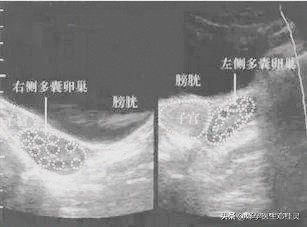

多囊卵巢综合征患者的B超检查单

5.双侧卵巢形态饱满,每平面看探及约10+个小卵泡,髓质回声略强。

4.右侧卵巢大小约3.5×2.9cm,最大乱拍大小约0.9×0.9cm。左侧卵巢大小约3.2×2.4cm,最大卵泡大小约0.7×0.7cm .